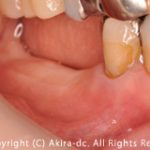

右下大臼歯部分の著しい骨欠損と炎症症状によりインプラント治療が可能な骨量の不足のため、下顎枝からブロック骨を移植し、骨量の再生後にインプラント治療を行なった患者さんです。

患者さんは、右下大臼歯の動揺を自覚していたものの長期に渡り経過を見られていました。歯列は、オープンバイト(開口)の歯列であり臼歯の負担荷重が著しく大臼歯の消耗、骨吸収が生て限界の症状を呈していました。オープンバイト(開口)のケースでは、臼歯の負担荷重が大きくインプラント治療や補綴治療においてリスクがあるため、歯列矯正を検討する必要もあると考えます。しかし、患者さんの年齢を考え歯列矯正は現実的ではないため、インプラント治療において重要となる頬側骨の確保と安定、質が高いかつ骨との結合の安定性の信頼度の高いインプラントと考え、スイス製のストローマンインプラントのティッシュレベルインプラントを選択しました。世界シェアもトップレベルのインプラントメーカーを選択することも重要と考えます。それぞれの患者さんに合ったインプラント治療を検討し、当医院の持ち得る知識から最適な治療を目指しています。手前の歯は、オールセラミック修復により機能改善し、咀嚼機能を可能な限り改善を目指しました。心を込めて取り組むことができましたことと患者さんのご協力を得られながら治療に集中できたことに大変感謝致します。

The patient was aware of the mobility of the lower right molar, but had been monitoring the progress for a long time. The dentition was an open bite, and the load on the molars was significant, leading to wear and bone resorption, which caused symptoms of limitation.

In the case of an open bite, the load on the molars is large, which poses risks for implant treatment and prosthetic treatment, so orthodontic treatment may also be considered. However, considering the patient's age, orthodontic treatment is not realistic, so we selected a tissue level implant from Straumann Implants, a Swiss company, as we believe that it is an implant that secures and

stabilizes the buccal bone, which is important for implant treatment, and is high quality and highly reliable in terms of the stability of the bond with the bone. We also believe that it is important to select an implant manufacturer with a leading global market share. We consider implant treatment that is suitable for each patient and aim to provide the best treatment based on the knowledge we have at our clinic. The front teeth were restored with all-ceramic restorations to improve function and chewing function as much as possible.